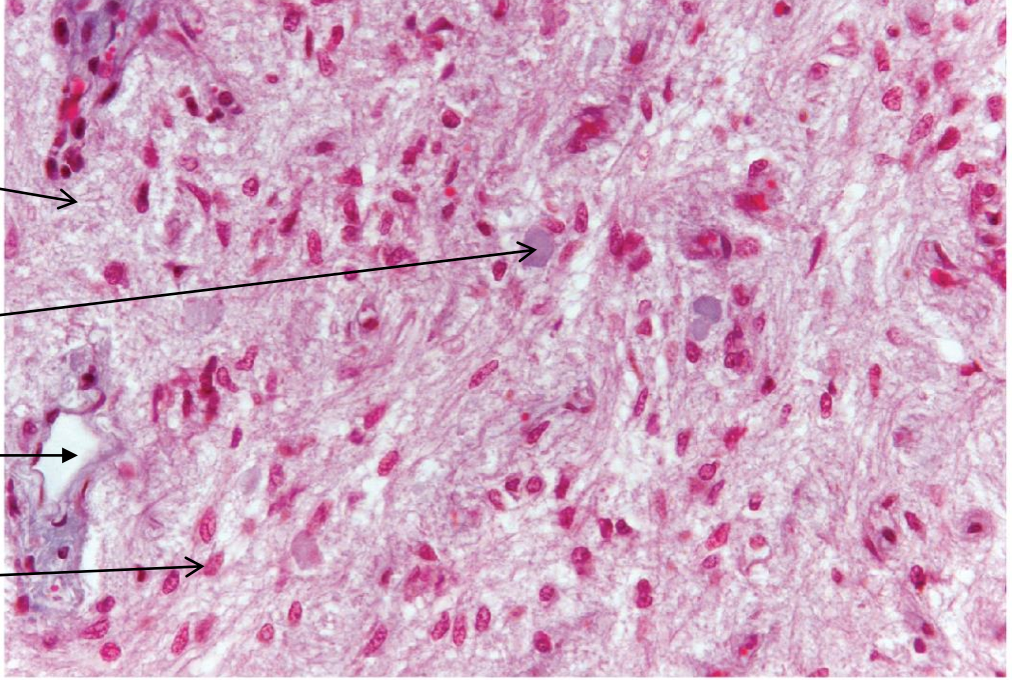

adrenal gland

adrenal gland: cortex

ZG=zona glomerulosa

ZF=zona fasciculata

ZR= zona reticularis